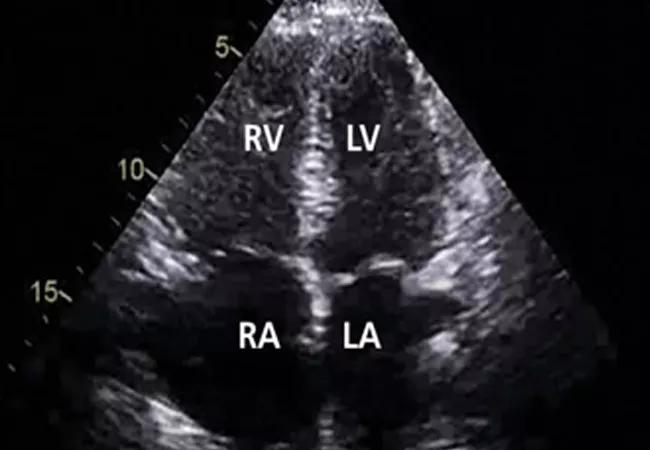

Echocardiographic views of a patient with pulmonary hypertension (left) and a patient without (right). Note the increased right ventricular-left ventricular ratio and right atrial enlargement in the patient with pulmonary hypertension.

The 2015 European Respiratory Society and European Society of Cardiology guidelines recommend using additional echocardiographic variables to determine the probability that a patient has pulmonary hypertension. While this recommendation is largely based on expert opinion, it supports the notion that right ventricular systolic pressure alone is not enough to determine the probability of pulmonary hypertension. Accordingly, patients with a right ventricular systolic pressure that is significantly elevated (> 50 mm Hg) or moderately elevated (> 40 mm Hg), along with other signs of right ventricular dysfunction (e.g., a dilated right ventricle or atrium, septal flattening), should be considered for additional diagnostic testing.